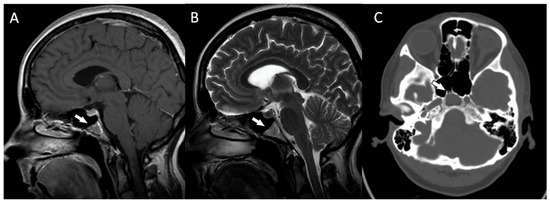

Postoperative MRIs showed minimal residual lesions within the sphenoid sinuses (Figure 4A–C). The 4-year follow-up of the patient revealed no clinical or radiological features of tumor recurrence.

Figure 4.

(A,B) The postoperative magnetic resonance T1-weighted and T2-weighted sagittal images and the postoperative magnetic resonance T2-weighted coronal image (C) showing some minimal residual lesions within the clival region (arrows).